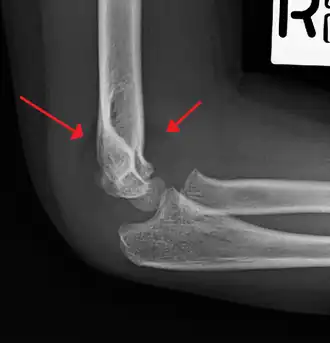

An elbow X-ray showing a displaced supracondylar fracture in a young child

A supracondylar humerus fracture is a fracture of the distal humerus just above the elbow joint. The fracture is usually transverse or oblique and above the medial and lateral condyles and epicondyles. This fracture pattern is relatively rare in adults, but is the most common type of elbow fracture in children.[1] In children, many of these fractures are non-displaced and can be treated with casting. Some are angulated or displaced and are best treated with surgery. In children, most of these fractures can be treated effectively with expectation for full recovery.[2] Some of these injuries can be complicated by poor healing or by associated blood vessel or nerve injuries with serious complications.

A supracondylar humerus facture is diagnosed by x-ray and the injured limb will be examined to assess the surrounding soft tissue, neurovascular status, and to identify any other injuries to the affected area.[5] Pain, swelling, and deformity near the elbow or arm area is common and a bleed near the fracture may result in an effusion in the elbow joint. With severe displacement, there may be an anterior dimple from the proximal bone end trapped within the biceps muscle. The skin is usually intact. If there is a laceration that communicates with the fracture site, it is an open fracture, which increases infection risk. For fractures with significant displacement, the bone end can be trapped within the biceps muscle with resulting tension producing an indentation to the skin, which is called a "pucker sign".